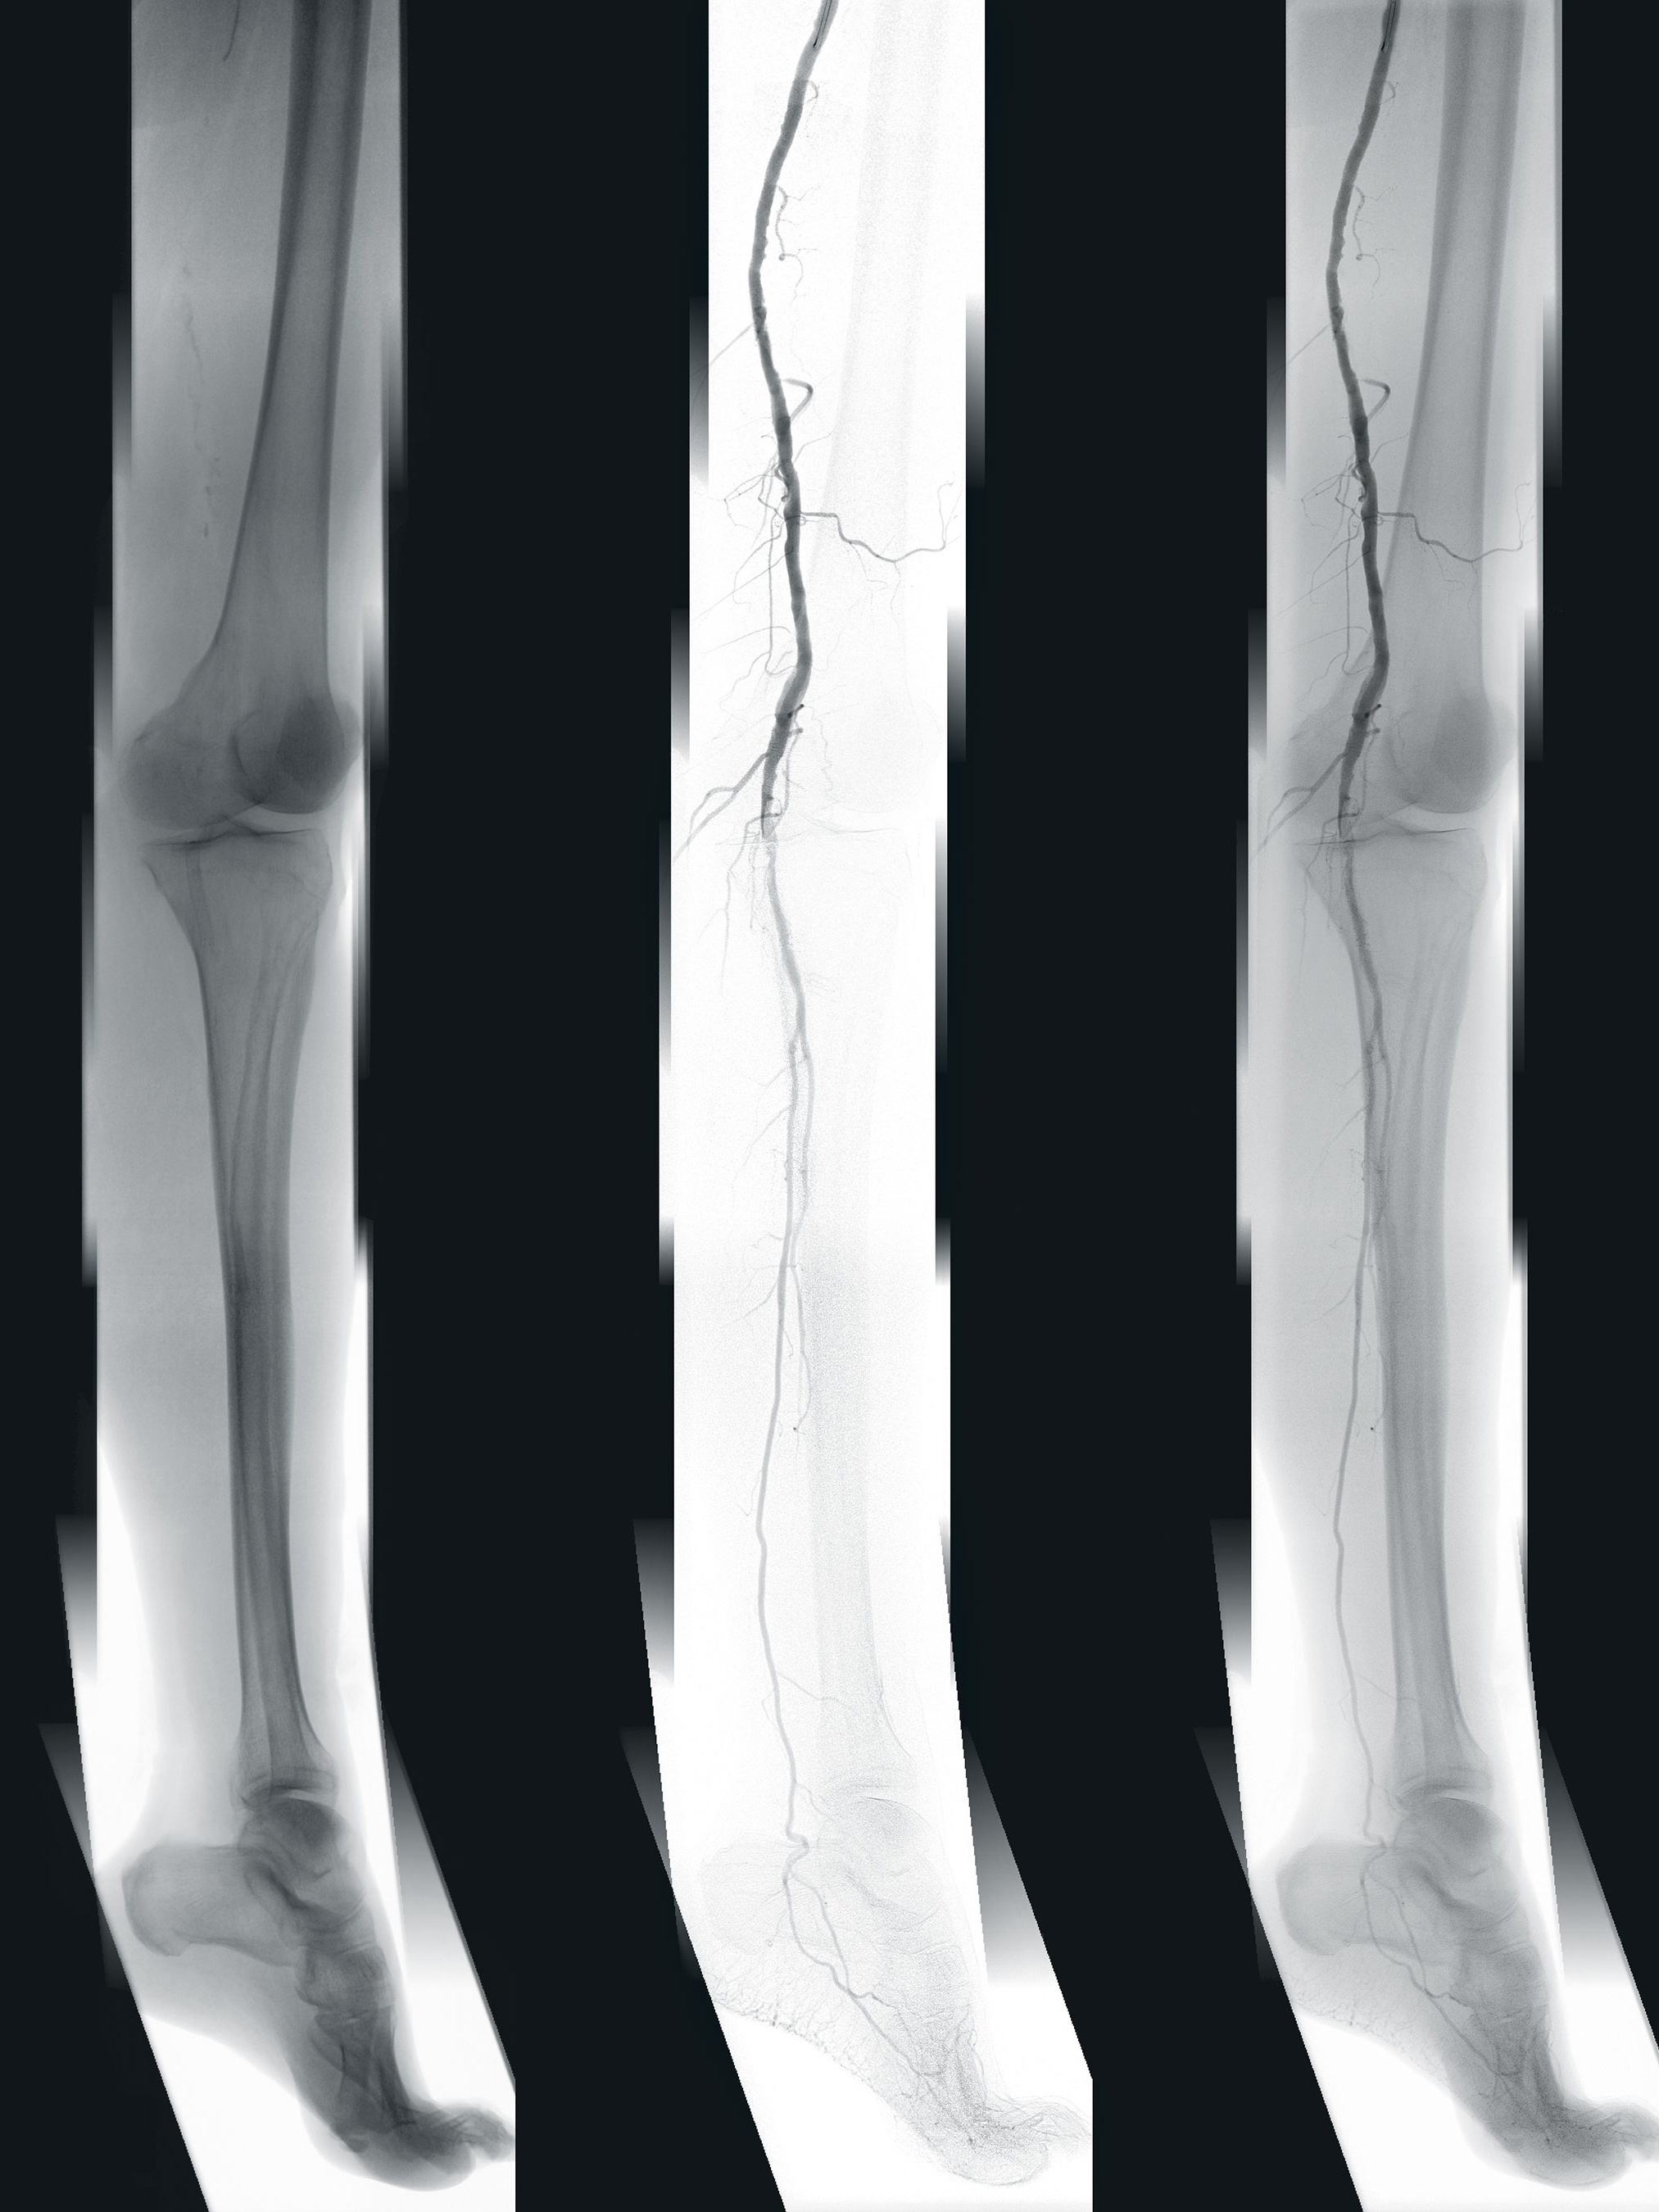

Time-consuming vascular surgery is on the agenda world-wide. Digital tools help efficiently evaluate clinical images prior to surgery. The EndoSize software solution enables accelerated, AI-based preparation of the procedure on the computer, leading to reduced use of radiation and contrast agents in the intraoperative phase. More precise treatment also minimizes the risk of complications.

Automated 3D segmentation of the target volume

An adaptive algorithm isolates the relevant anatomical region within the image data and highlights it from the surrounding structures. Surgeons benefit from a clear visual representation of the surgical field. Vascular anomalies such as aneurysms and stenoses can be reliably identified.

Centerline for precise measurements

With just a few clicks, the intelligent software quickly and easily calculates the centerline. This is displayed as a virtual axis running along the main arteries. It can also be extended to include relevant arteries. It is the starting point for automated and accurate generation of relevant measurements such as length, angle, volume, diameter and clock position.